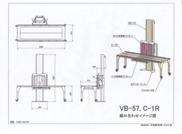

大林製作所製ホルダー AS社用ホルダー